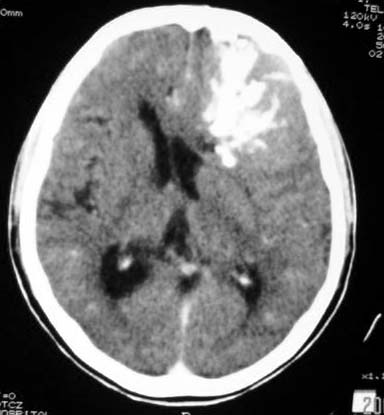

标题: CT7268:左额顶部病变增强片. [打印本页]

标题: CT7268:左额顶部病变增强片.

比较典型的少枝胶质细胞瘤ct表现,局部额骨垂直板有侵蚀变薄。

左侧额顶叶有条带状钙化的不规则形占位,增强呈不均匀轻度强化,局部颅骨受侵蚀变薄,典型的少支胶质细胞瘤。

比较典型的少枝胶质细胞瘤ct表现,局部额骨垂直板有侵蚀变薄